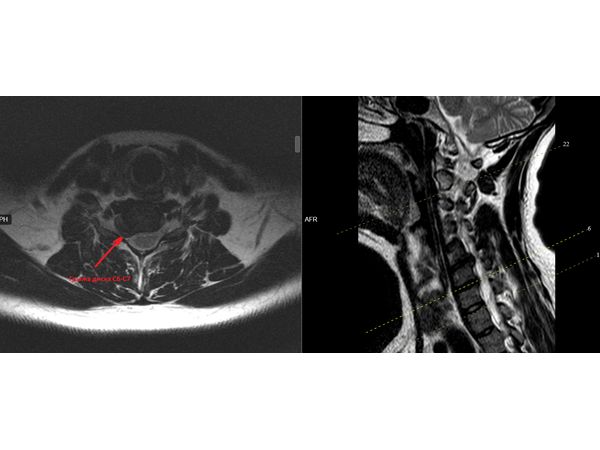

МРТ шейного отдела показал признаки остеохондроза и грыжу диска С5-С6 (6 мм), С6-С7 (4,5 мм).

Дорсопатия шеи на фоне остеохондроза. Выраженный мышечно-тонический синдром. Обострение цервикалгии.

Вторичный корешковый синдром справа на фоне грыжи диска С5-С6, С6-С7 со снижением чувствительности и силы в правой руке.